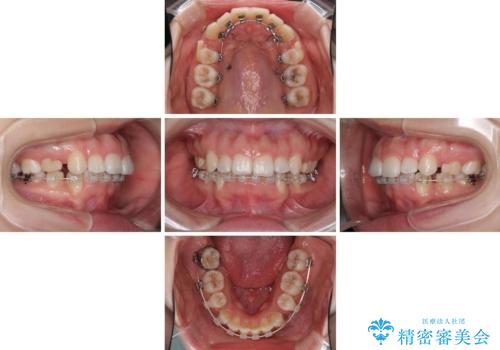

- ハーフリンガル

- 前歯のデコボコと上顎の前突感による口の閉じにくさを気にして来院された患者様です。

目立たない装置を希望されたので、上顎が裏側装置のハーフリンガルを選択し、上下左右の小臼歯(計4歯)を抜歯して矯正治療を行うこととしました。

治療期間の目安は2年半~3年間でしたが、咬み合わせにより上顎装置が頻繁に脱落してしまい、治療期間が長期化してしまいました。

期間はかかったものの、口元の張り出し感や歯のデコボコが解消され、患者様には大変満足していただけました。